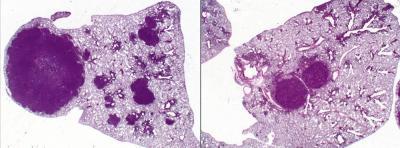

Salk scientists found that the diabetes drug phenformin was effective at reducing tumor size in mice with lung cancer. The image on the left shows tumors (dark purple) treated with a placebo (left) compared to those treated with phenformin (right).

That led Shaw and his team to a class of drugs called biguanides, which lower cellular energy levels by attacking the power stations of the cell, called mitochondria. Metformin and phenformin both inhibit mitochondria; however, phenformin is nearly 50 times as potent as metformin. In the study, the researchers tested phenformin as a chemotherapy agent in genetically-engineered mice lacking LKB1 and which had advanced stage lung tumors. After three weeks of treatment, Shaw and his team saw a modest reduction in tumor burden in the mice.

Continuing the study between Salk and UCLA, Shaw and Shackelford coordinated teams in both locations to perform further testing on mice with earlier stage disease, using cutting-edge imaging technologies just like those used on lung cancer patients in the clinic. They found that early phenformin treatment causes increased survival and slower tumor progression in tumors lacking LKB1, but had no significant benefit for tumors with alterations in other lung cancer genes. This specificity in treatment fits with an emerging approach in cancer treatment nationwide, known as personalized medicine, in which the therapies for each patient are selected based on the genes altered in their tumors.